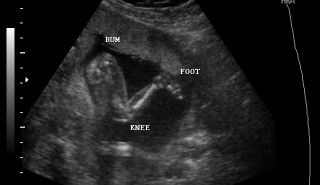

I'm 20 weeks and 4 days and it's our anomaly scan today. We found out na may Amniotic Band Syndrome si baby. Natunaw yung brain and left hand nya because of too much Amniotic fluid. Di naman cause of genetics and there was nothing to do to prevent it. Even tho na maipanganak ok sya di ko maiiuwi because ilang oras lang mabuhuhay ang baby girl ko. I'm so sad and mas malungkot si hubby iyak sya ng iyak. He knows na di ako umiiyak infront of others, but di ko mapigilan when he started crying. So we decided to terminate my pregnancy on Monday. She's kicking rn while I'm crying :(( We already picked out a name and we started buying stuff for her :(( Ive prayed every night na sana maging healthy ,normal and safe si baby but I dont know what i did wrong. We took extra precautions pa nga :( Nakakalungkot ng sobra. I just wanna share and ask if gano katagal kaya ako mabubuntis ulit? I feel like I NEED to be pregnant again, I NEED to hold my baby kasi di ko makakaya yung lungkot. Btw I'm 21 and my hubby is 24. Edit: I already terminated my pregnancy mga mamsh :( it was hard pero atleast my baby girl is dancing in heaven with her grandaddy, no more pain. Thank you for all your comments, nakakaiyak I'm okay now physically but emotionally hindi pa, I always cry every night when I pray. I miss my active baby and my baby bump. We decided to call her Leilani โ™ก it's a Hawaiian name means heavenly flower. I also decided na mag vacation muna sa pinas, para mawala lungkot ko. It'll be sad and painful seeing my healthy baby nephews but they'll make me feel better. Labyu mga mamsh, thank you all for being with me on this painful journey.